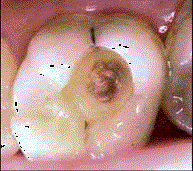

问题 患者女性,20岁。因左侧后牙进食时嵌塞食物疼痛就诊。检查:左上6面龋洞,探洞底敏感,叩(-),冷刺激入洞后疼痛,去除刺激立即消失,热测同对照牙。该牙诊断可能为 ( )

选项 A.浅龋 B.中龋 C.深龋 D.慢性牙髓炎 E.急性牙髓炎

答案 C